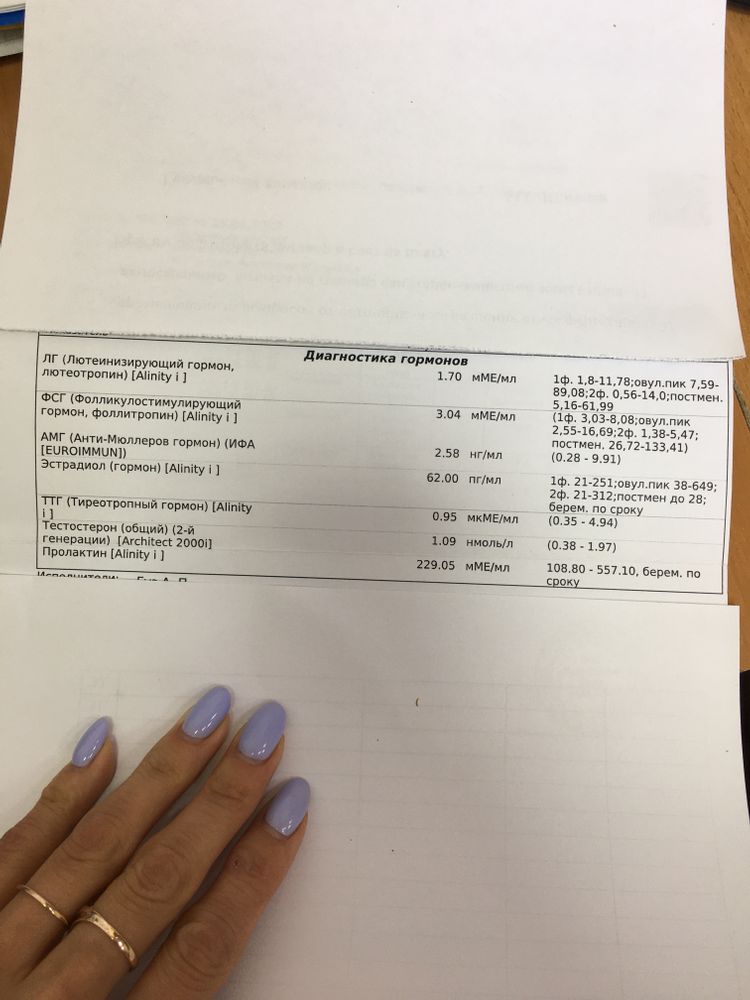

Планируем Б. Несколько месяцев в пролёте. В апрельском цикле была овуляция 100% (тест подтвердил и выделения соответствующие были), но муж был в командировке. В майском цикле делала тесты по 2 раза в день, но овуляцию так и не поймала, да и выделений не было нужных. Поэтому в этом (июньском) цикле решила повторно сдать анализы на 4 день цикла на ЛГ, ФСГ, АМГ, ТТГ, Тестостерон, Пролактин (ранее в начале года сдавала на эти гормоны и все было в норме, кроме Пролактина и Прогестерона, но эти гормон я выровняла (делала вагинально Утрожестан). Пришли сейчас результаты и виде что у меня понизился ЛГ и ФСГ. Решила за одно сходить на УЗИ ОМТ, так как побаливает живот будто должны начаться месячные (что странно так как они прошли 5 дней назад). До овуляции рано, обычно у меня овуляция на 19-20 ДЦ бывает (решила тесты даже сразу после месячных начать делать чтобы уж наверняка в этом цикле не упустить)

В итоге сходила вчера на УЗИ и толком ничего не поняла, врач не пояснила. Сказала что не может понять, как будто должна скоро начаться овуляция но при этом эндометрий маленький. Также поставила под вопросом МФЯ. Сказал сделать ещё раза фолликулометрию и иди к гинекологу с результатами.

Девочки посмотрите пожалуйста мои анализы и результаты УЗИ. Может вы что-то поймёте и мне объясните. Не могу ни как себя успокоить, переживаю. Даже работать не получается(